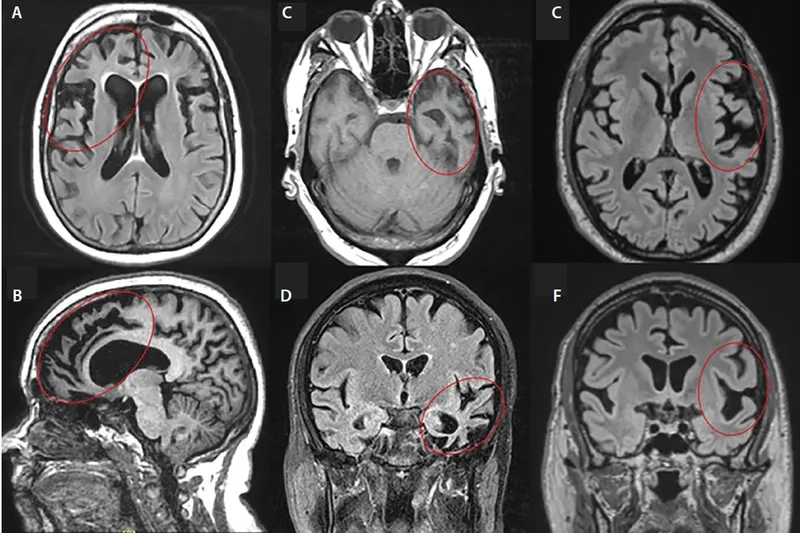

Understanding the behavioral frontotemporal dementia symptoms